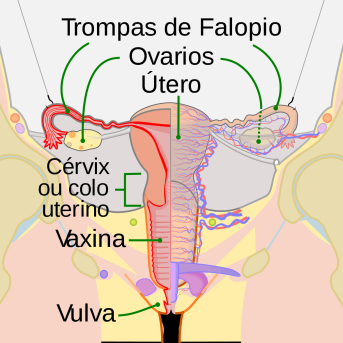

O corpo feminino secreta diversos tipos de muco durante... Continuar Lendo

Preocupação inevitável de todas as gestantes no primeiro trimestre, ... Continuar Lendo

O corpo feminino vai se adequando a cada mudança do ciclo... Continuar Lendo